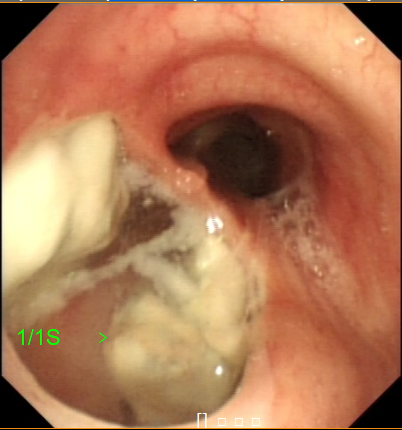

在我院经过支气管镜检查发现一个巨大气管食管瘘,主瘘口旁还有两个小瘘口,经测量瘘口近端至远端距离长达4cm,胃内容物源源不断通过瘘口反流至肺部造成严重的吸入性肺炎。困扰老人许久的症结终于找到。

图1:通过巨大瘘口清晰可见食道内坏死组织